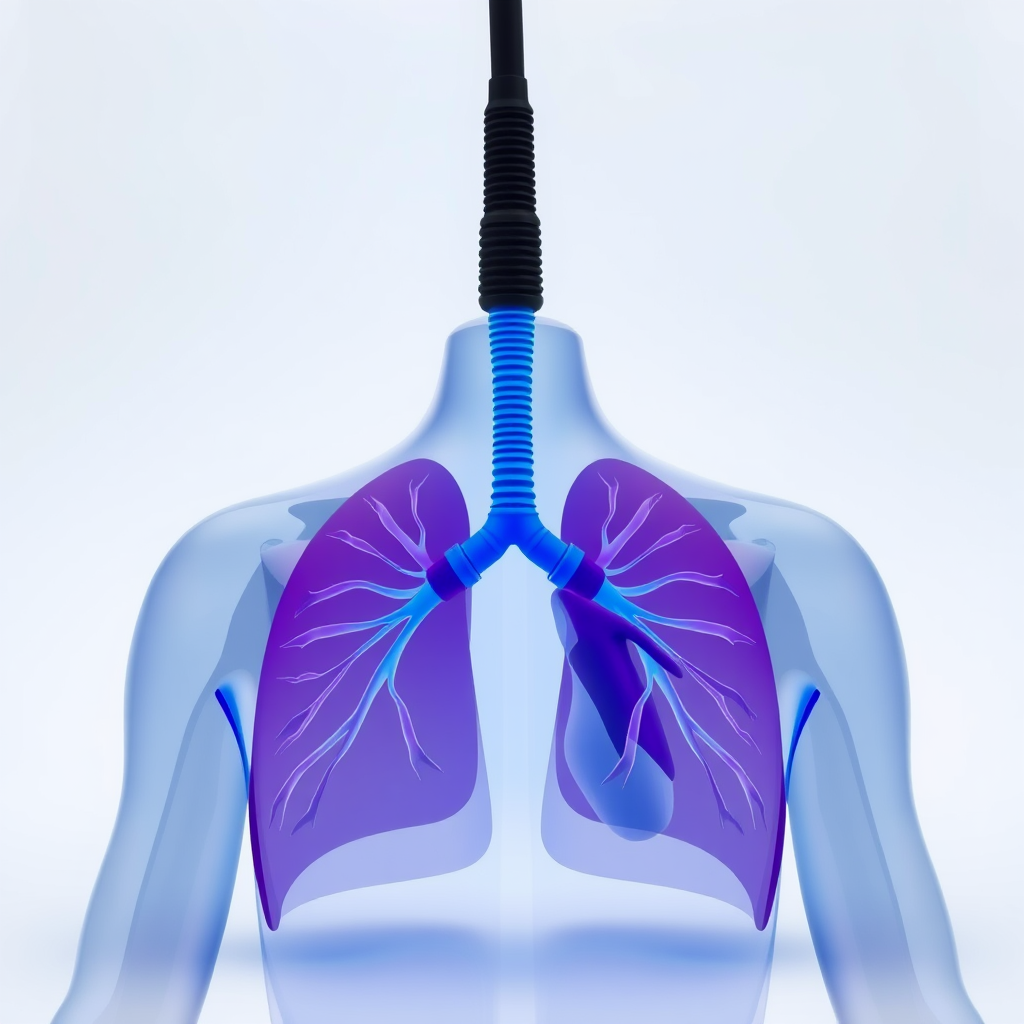

A fisioterapia cardiorrespiratória em São Paulo oferece uma série de benefícios significativos para a saúde cardiovascular e respiratória.

Esse tipo de fisioterapia é especialmente importante para pessoas que enfrentam desafios relacionados ao coração e aos pulmões.

Melhora da Capacidade Pulmonar

A fisioterapia cardiorrespiratória em São Paulo é voltada para ampliar a capacidade pulmonar.

Isso ocorre por meio de exercícios específicos e acompanhamento profissional.

Prevenção de Complicações Respiratórias

A fisioterapia cardiorrespiratória em São Paulo também atua de forma preventiva.

Isso é relevante para pacientes com condições respiratórias crônicas.